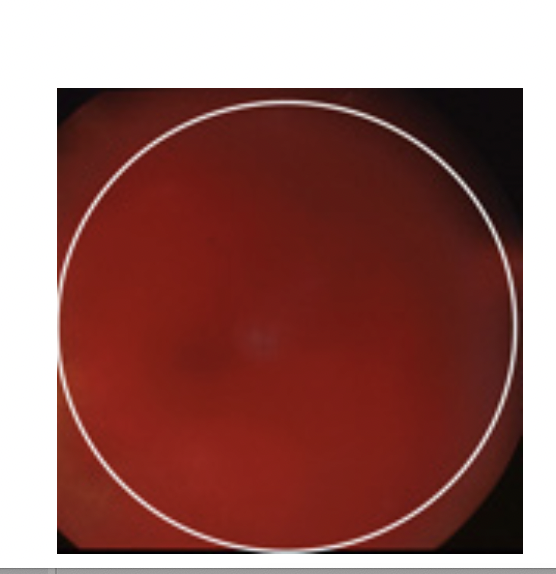

Oftalmoskopi af højre øje: Se foto.

Hvad er din tentative diagnose?

- Grå stær på højre øje efter tidligere slag mod øjet

- Hyfæma på højre øje

- Glaslegemeblødning på højre øje

- Sekundært åbenvinklet glaukom på højre øje

- Proliferativ diabetisk retinopati på højre øje

- Glaslegemeblødning på højre øje